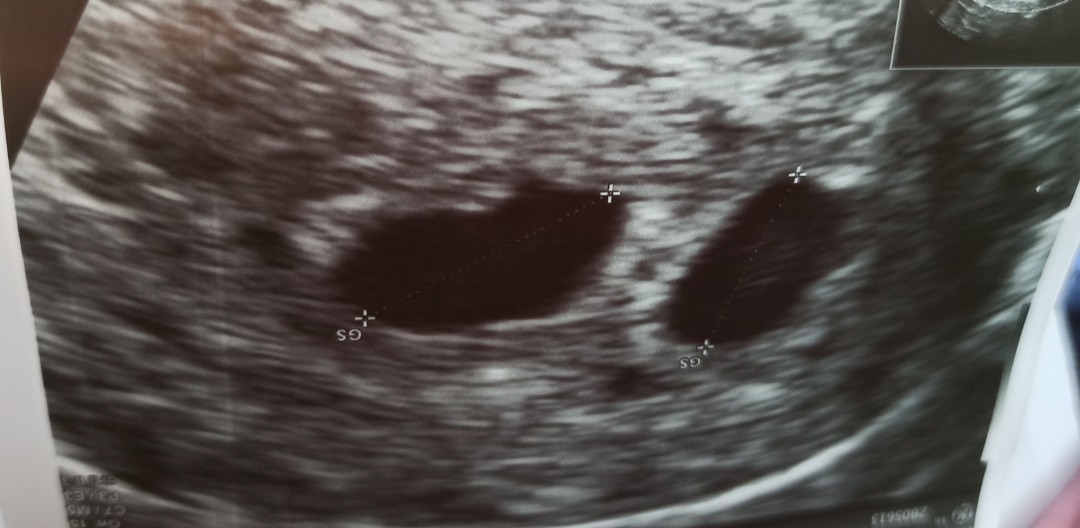

Dla dziewczyn, które chciałby zobaczyć jak wygląda sam początek ciąży bliźniaczej. Tu zdjęcie gdzie są tylko pecherzyki. Nasze pierwsze, jeszcze bez zarodków i serduszek. Pęcherzyki są rowne, regularne